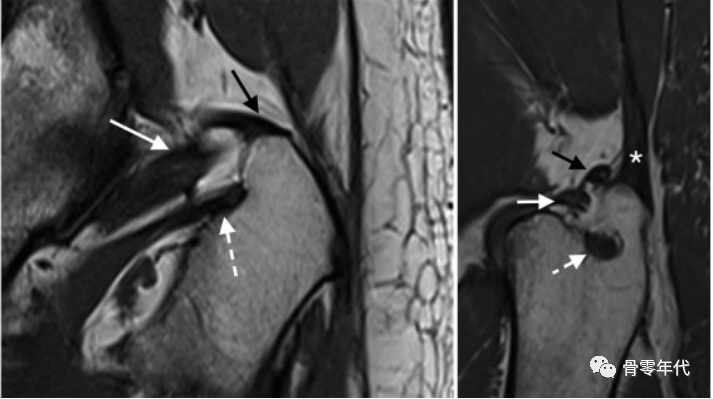

在T1加权像上,一位79岁的男性,在全髋关节置换术的后路手术后,有明显的短外旋肌腱病变。(a)梨状肌腱变薄(黑色箭头),闭孔外肌腱变粗和磨损(虚线箭头)。(b)闭孔内肌腱撕裂和回缩,肌肉严重萎缩(箭头)。